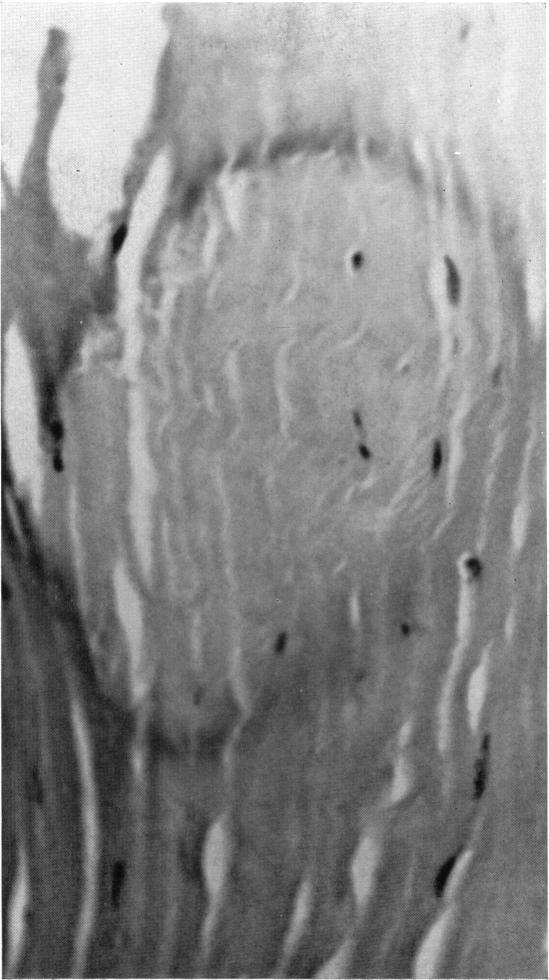

Hereditary deep dystrophy of the cornea (polymorphous).

Trans Am Ophthalmol Soc. 1969;67:235-64.